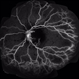

- CMV

- Condition/keywords

- vasculitis

- 70-year-old white female, III CMV, 20/40: OK; 5/200: infilesatire, vasculitis viluitis.